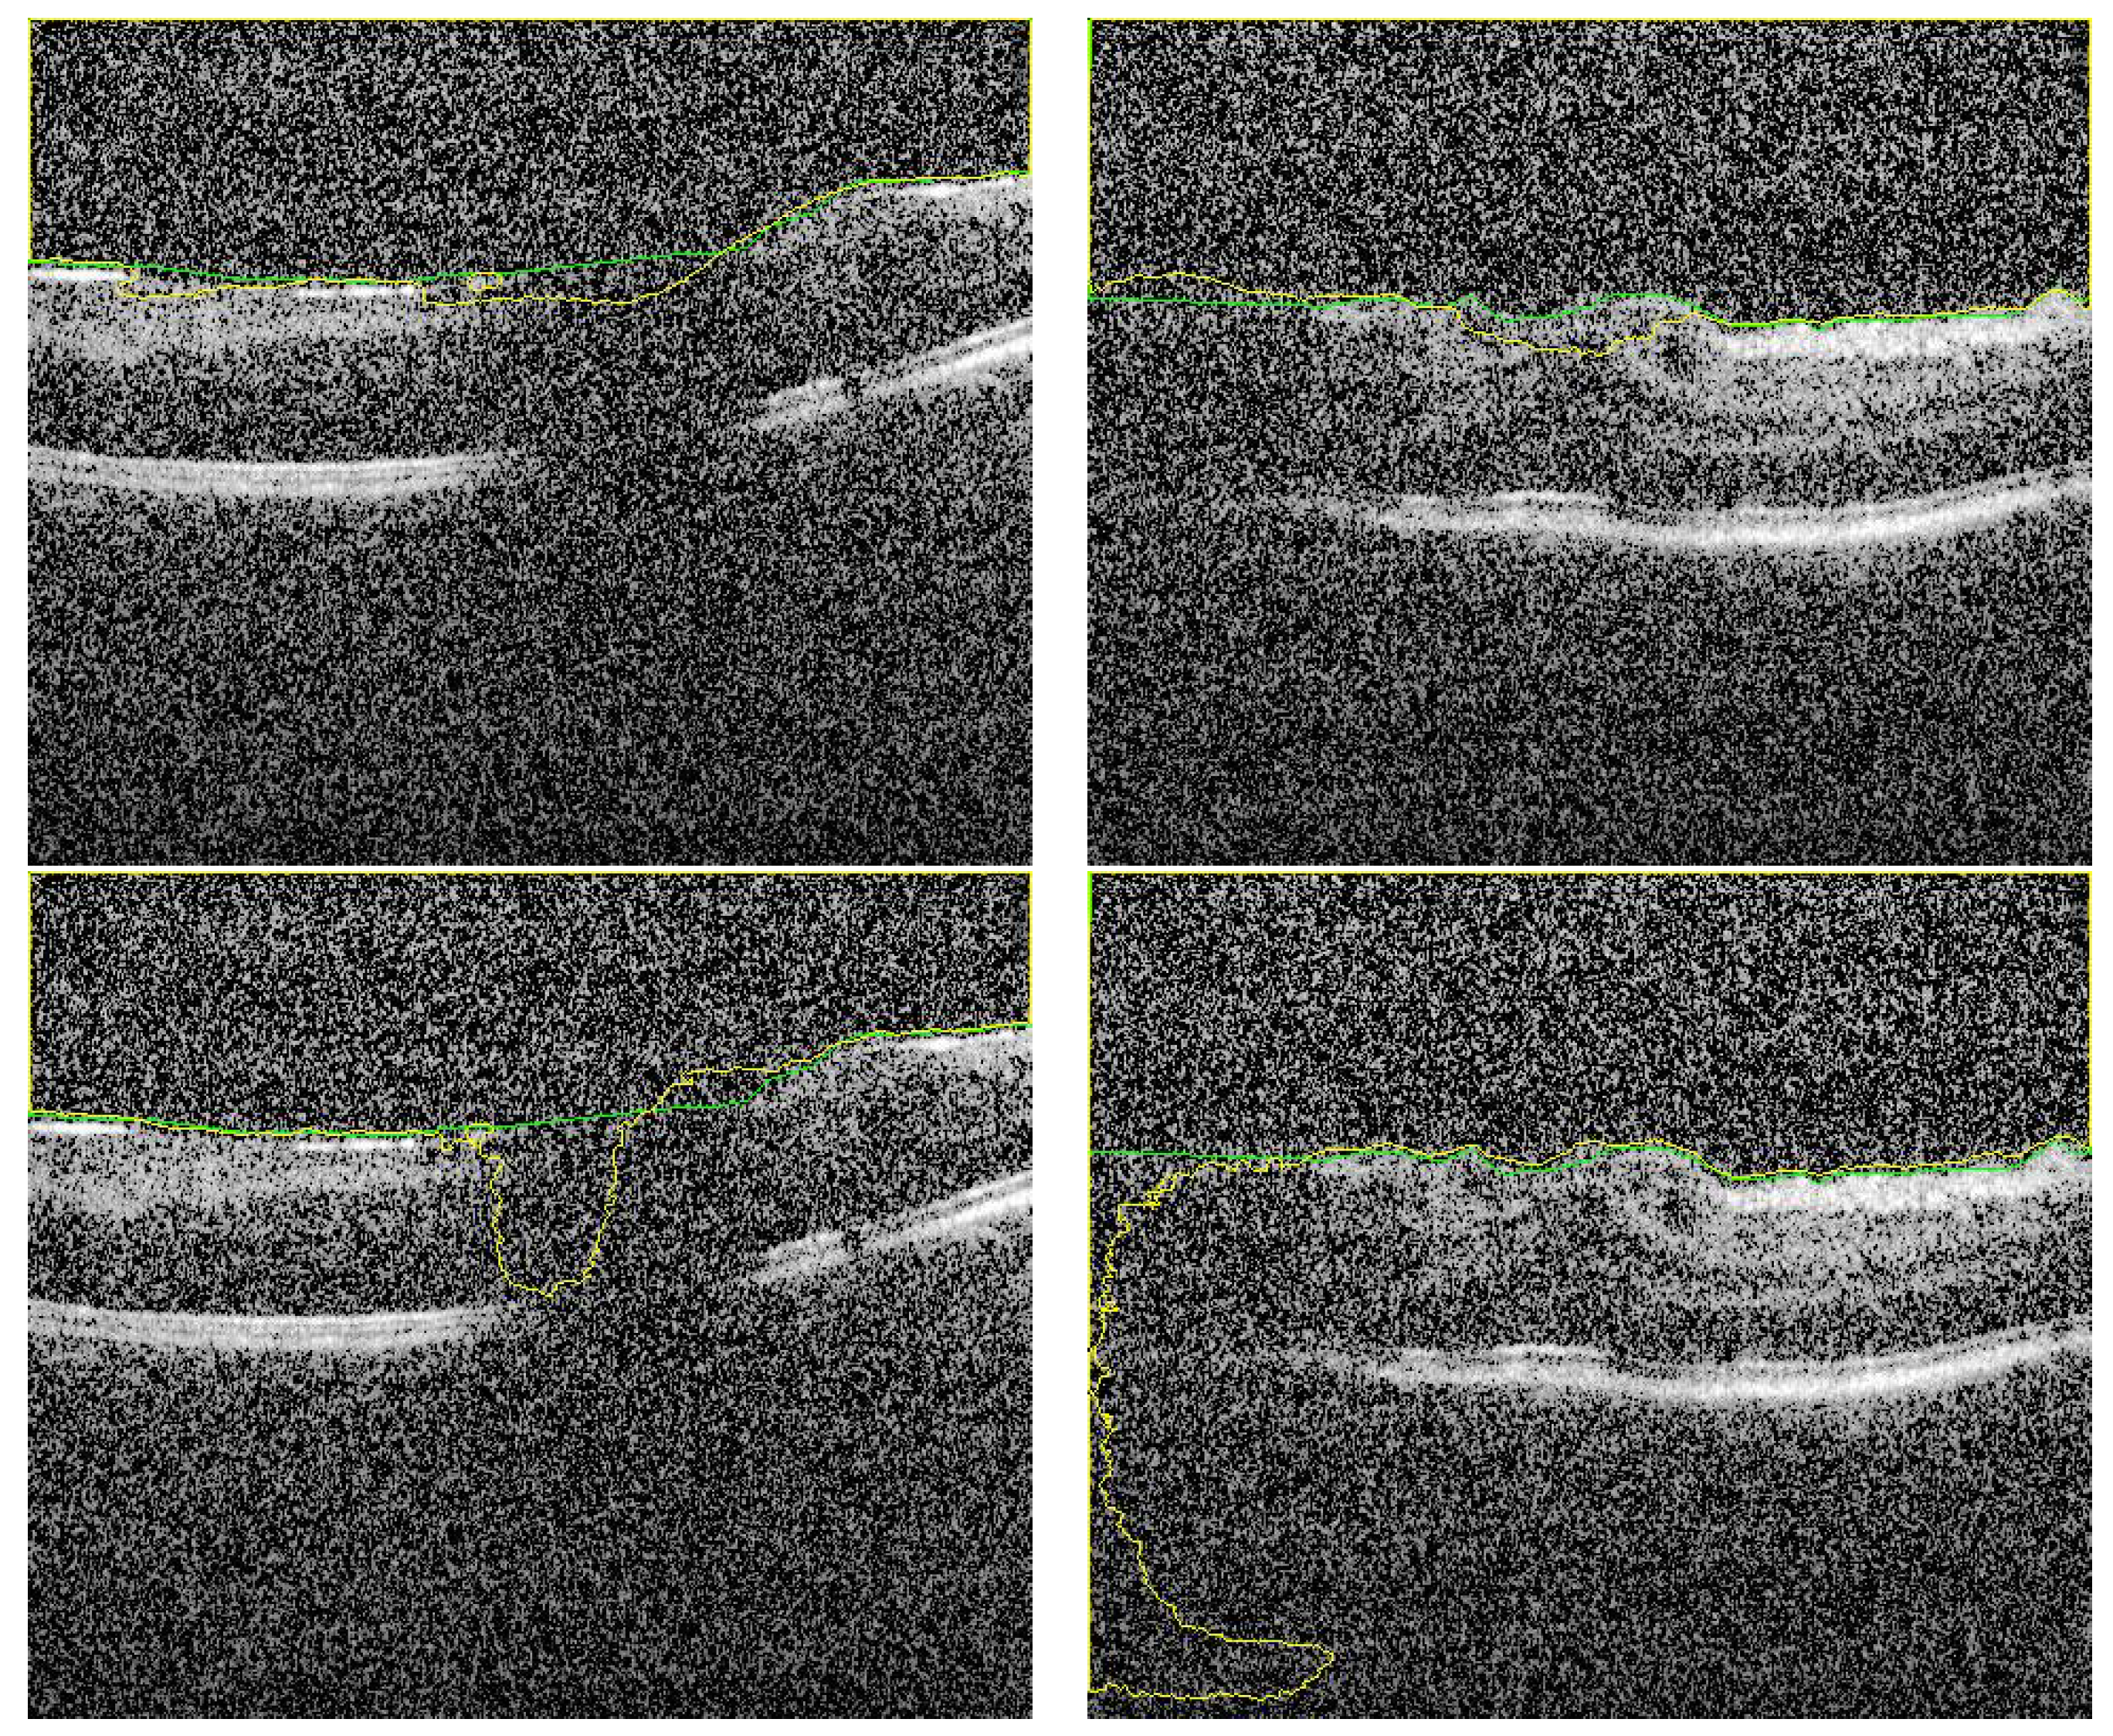

3.2. Fused Image Construction

3.3. Overall Segmentation Evaluation